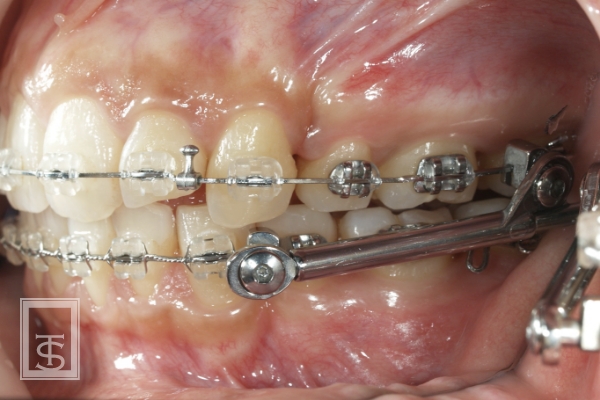

ハーブスト装置(Herbst appliance)

下顎骨成長促進、下顎骨前方誘導を行う装置となります。